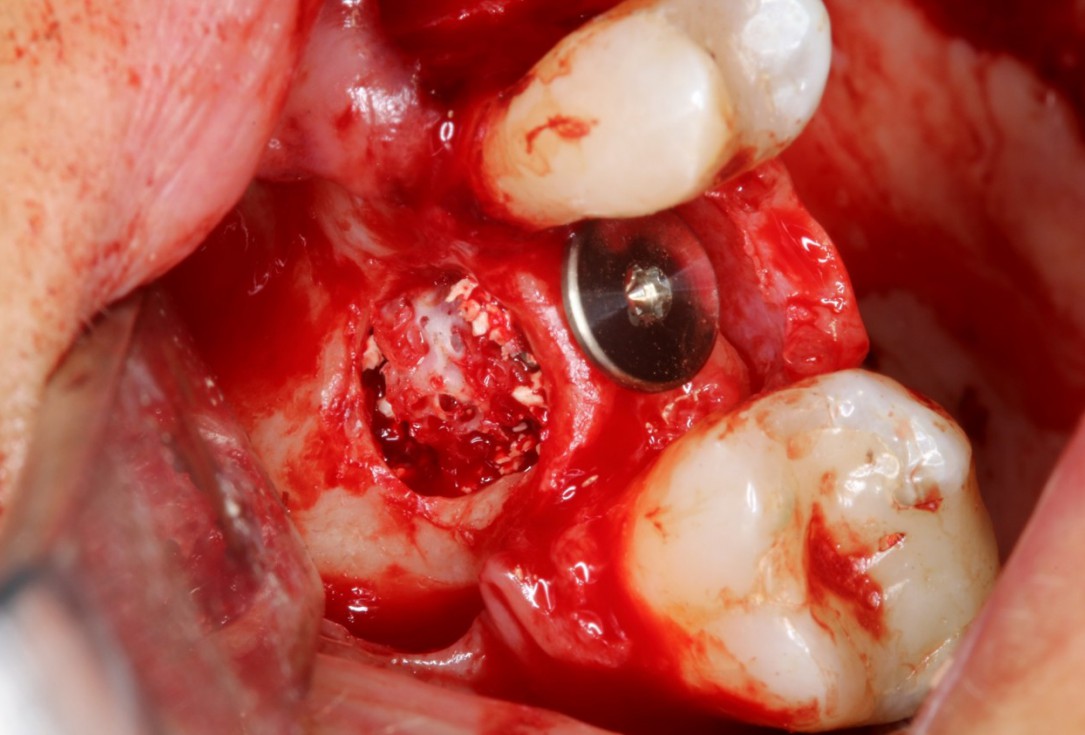

Clinical situation: 71-old patient with atrial fibrillation and Warfarin medication